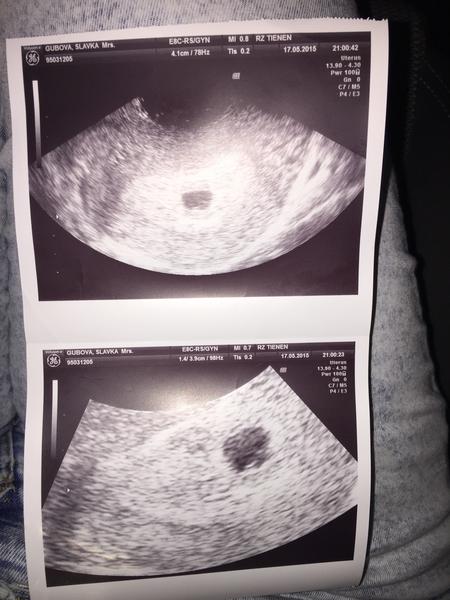

@mmoni89 no ja som objednaná môjmu až 26teho 🙂 ale tak , ked už som bola na pohotovosti , tak ho kukli 🙂 a som úplne happy z neho 🙂